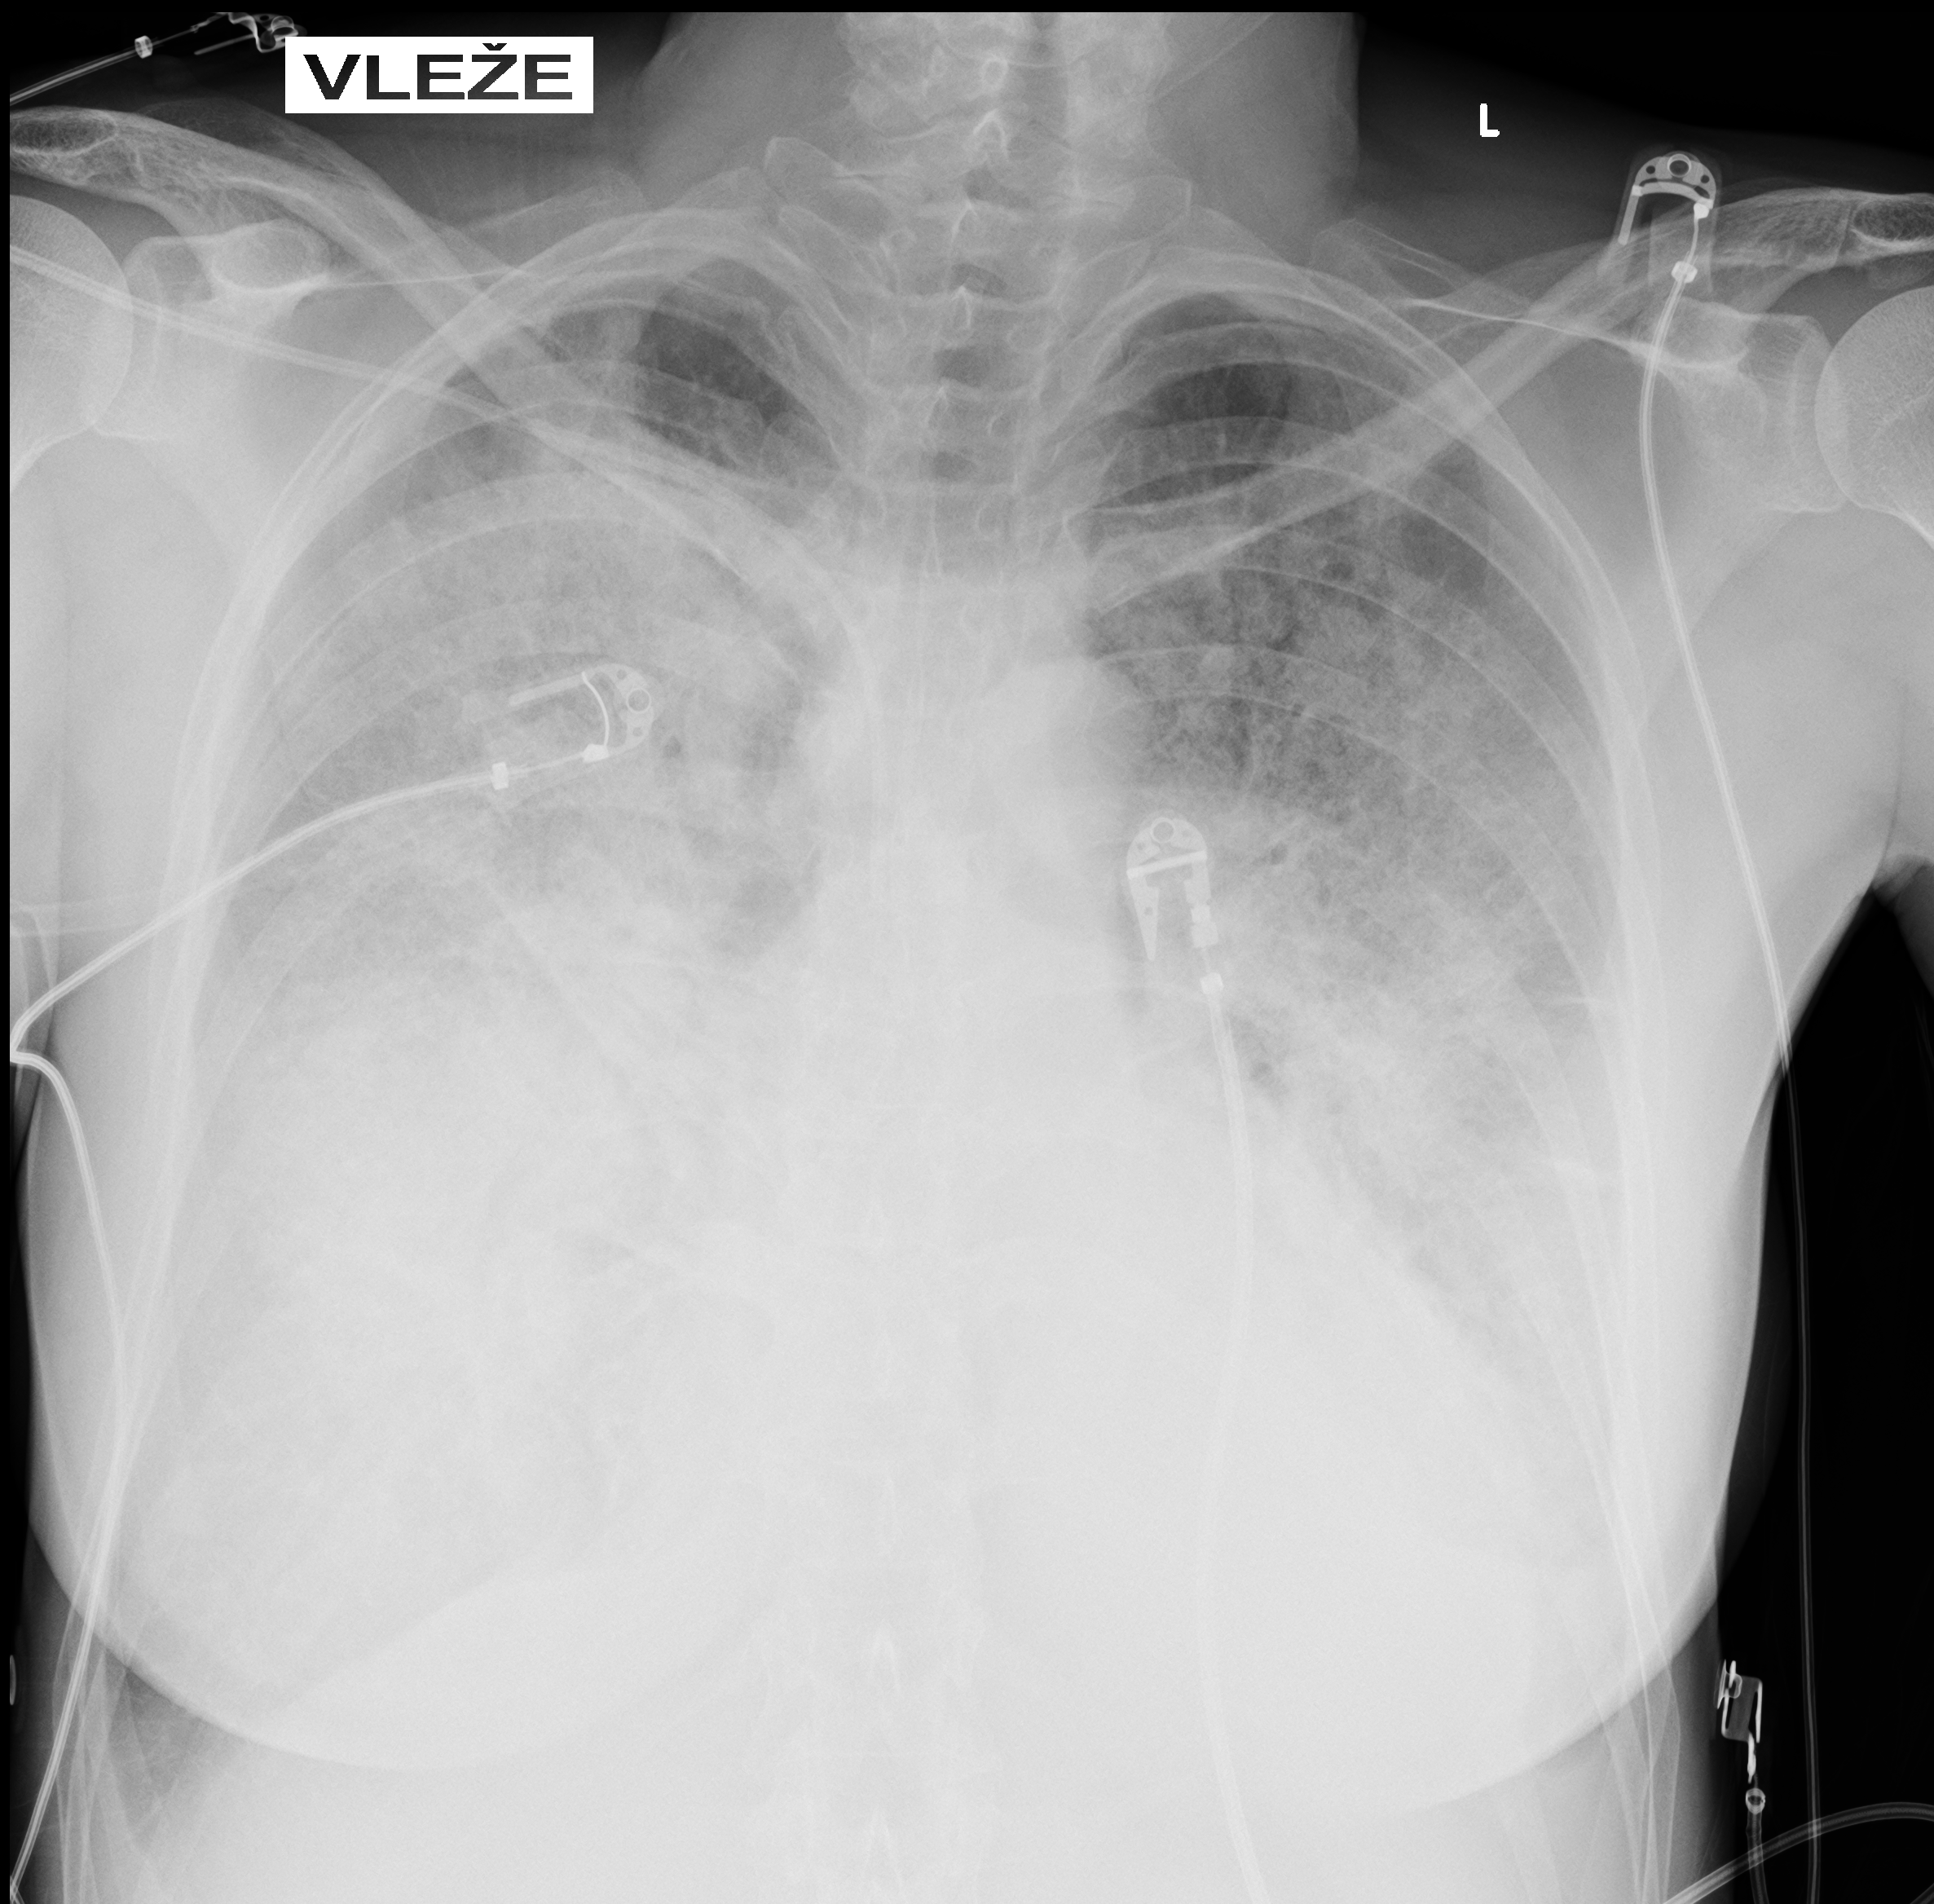

Chest X-ray on admission:

Markedly reduced bilateral transparency with perihilar opacities suggestive of pulmonary edema vs. early ARDS. Possible right-sided consolidation. Small pleural effusions not excluded. Cardiac silhouette enlarged.